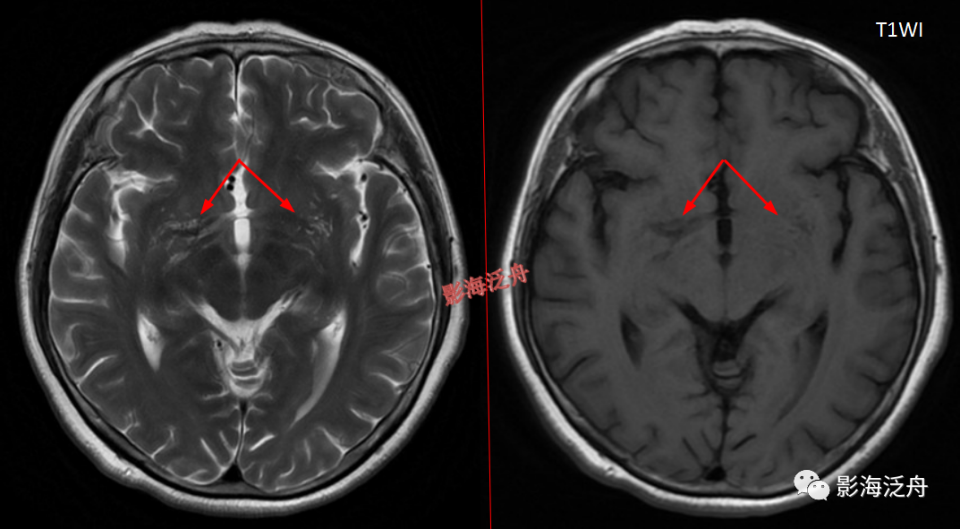

I型-基底节型:扩大VR腔隙呈对称性分布于双侧基底节区(红箭),左侧较大呈圆形,右侧较小呈斑点状。基底节型扩大VR腔隙好发于基底节下部,尤其是前联合层面(黄箭所指为前联合)。